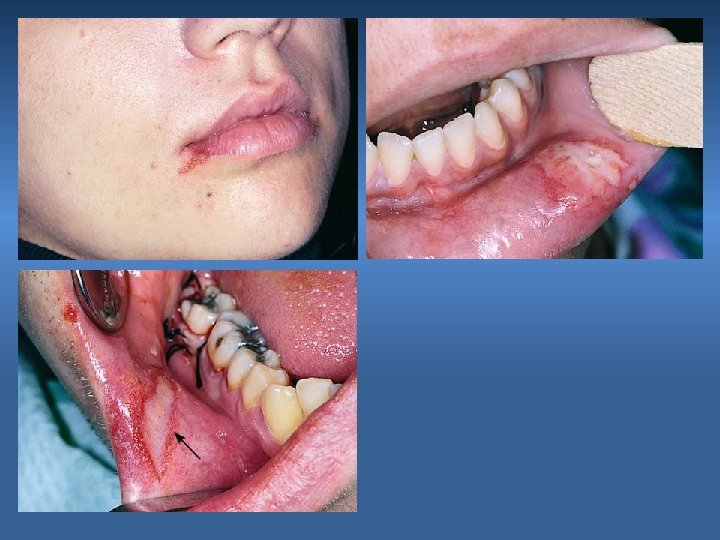

2. Puncture Wound of Soft Tissue Cause Instrument Slippage Prevention Controlled force Management Suturing to prevent infection & allow healing to occur

3. Stretch or Abrasion Injury Cause Bur shank or retractor injury Prevention Care Management Keep it moist ( ointment ) Heals within 5 – 10 days